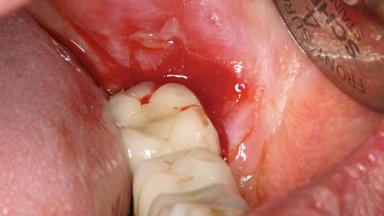

This case describes the ongoing management of a 64-year-old healthy, non-smoking female patient with erosive oral lichen planus (OLP) affecting the gingivae and the buccal and lingual mucosa. The peri-implant mucosa was also affected subsequent to implant placement. The patient had osseointegrated implants (four in the maxilla, four in the mandible) placed following extraction of hopeless teeth and a healing period. The patient had a history of OLP prior to implant placement and had been referred to an oral-medicine specialist for definitive diagnosis and treatment. She exhibited generalized oral mucosal involvement. Following a clinical assessment, biopsy, and blood tests, she was treated with topical corticosteroids. Systemic prednisolone was reserved for severe flare-ups. Amphotericin lozenges were used in combination with corticosteroid treatment to prevent the development of oral candidiasis.

Soft Tissue Anatomy Intact Defective